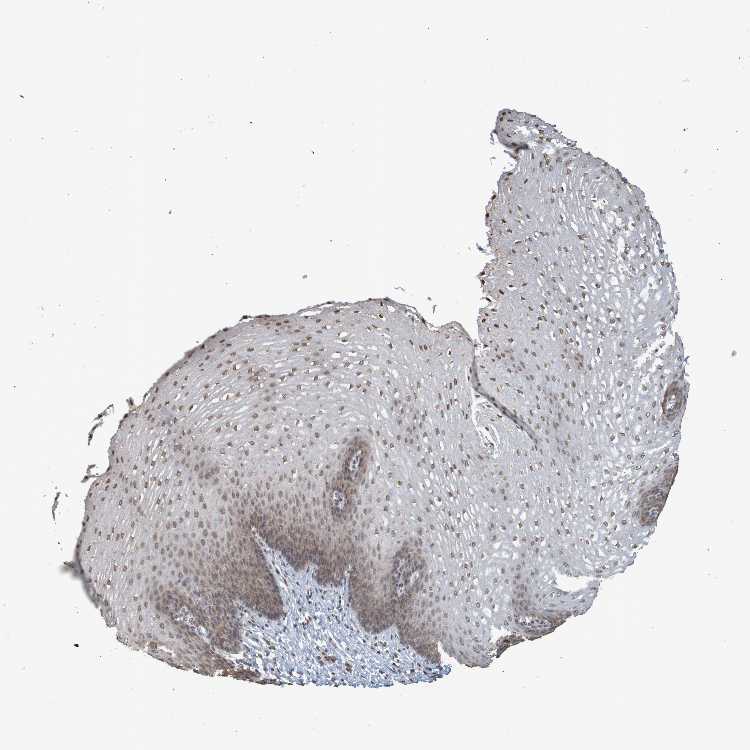

ESOPHAGUS - Antibody stainingi

Antibody staining in the annotated cell types in the current human tissue is reported as not detected, low, medium, or high, based on conventional immunohistochemistry profiling in selected tissues. This score is based on the combination of the staining intensity and fraction of stained cells.

Each image is clickable and will lead to virtual microscopy that enables deeper exploration of all samples and also displays staining intensity scores, fraction scores and subcellular localization as well as patient and tissue information for each sample.

Antibody CAB011197

Squamous epithelial cells Medium